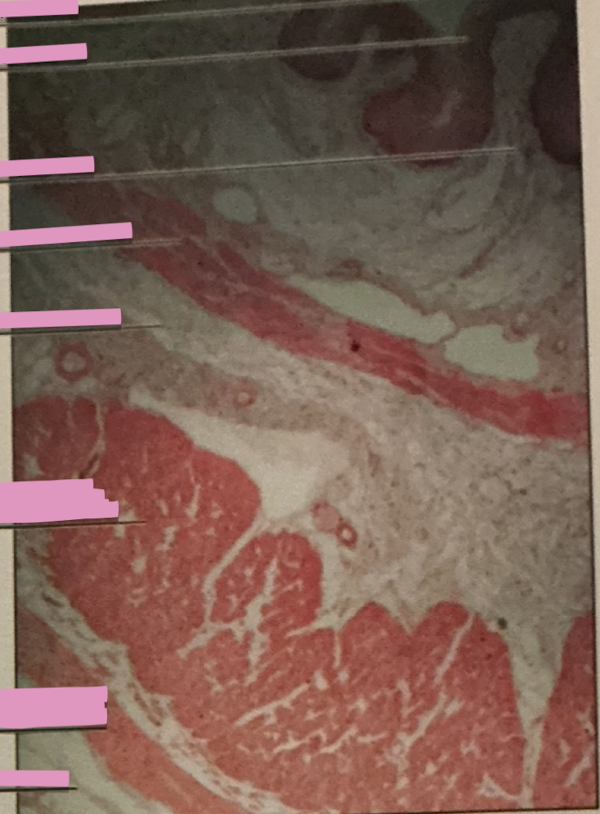

lympatic vessel valve

lymph node

lingual tonsil

palatine tonsil

retrograde flow

flow of lymph b/w nodes or organs relies on skeletal muscle and one-way valves to prevent __________

B cell mitosis

each lymph follicle w/in each lymph node is active center for ___________

dendritic cells

______________ capture antigens and bring them to lymph nodes

tonsils

collections of lymph tissue

back of mouth, tongue, nasopharynx

three tonsil locations

tonsils

_____________ have several lymphoid nodules(covered with stratified squamous epithelium) w/ germinal centers